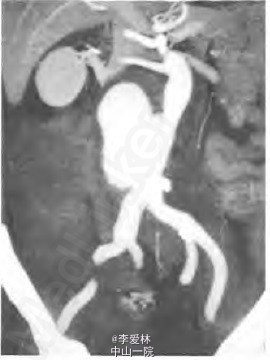

急查血管彩超提示腹主动脉瘤破裂;急诊CT血管造影(computed tomography angiography,CTA)提示IAAD和右髂总动脉夹层动脉瘤并右腹膜后大血肿.其中IAAD 7cmx6cm大小,裂El位于腹主动脉中段。右髂总动脉夹层动脉瘤5.5cmx5cm大小,裂口位于右髂内、外动脉分叉处。

腹主动脉夹层动脉瘤破裂,予以急诊行腔内修复术(endovascular aortic repair。EVAR)。分别在腹主动脉和右髂总动脉植入一个直管型覆膜支架,将2个裂口封堵。